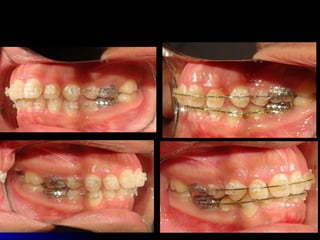

ANTES Y AHORA

Corregir patrón hiperdivergentey sonrisa gingival: Cirugía Corregir arco superior atrésico: Con arcos prefabricados Corregir vestibuloversión de incisivos superiores e inferiores: Sin extracciones Corregir mordida profunda y curva de Spee profunda: Con arcos de Nitinol Plan de tratamiento

Plan de tratamientoTiempo de tratamiento: Aproximado 1 año Tipo de aparatología: Ortodóncico: Aparatología fija Anclaje: Mediano